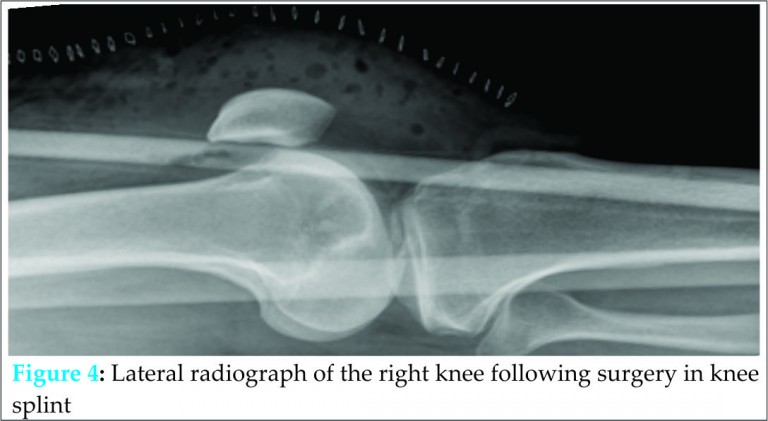

Our patient was subsequently taken to theatre where one final attempt of closed reduction was carried out under general anaesthetic and muscle relaxation. Ultimately, this failed and an open reduction was performed. The patient was positioned supine and an anterior midline skin incision was used. Complete rupture of the medial patellofemoral ligament (MPFL) was identified with the patella situated lateral to the lateral femoral condyle, everted by approximately 100 degrees. There were no visible deficiencies of the femoral condyles or the patellar articular surface. The patella was carefully reduced by direct manipulation. Following manipulation, the knee joint was washed out with normal saline and the medial patella retinaculum was repaired. After the repair, patella tracking was satisfactory with full range of flexion and extension.

Post-operative radiographs confirm the patella in a satisfactory position in the antero-posterior and lateral planes (see Figs. 3 and 4). The patient was placed in an extension splint for comfort purposes immediately post-operatively. No weight bearing restrictions were applied. Early mobilization was encouraged after 5 days and the patient was referred for early physiotherapy. At 3 months follow-up, our patient had no further episodes of dislocation, full range of knee extension and flexion, and normal patella tracking. A hypermobility assessment at this stage revealed a Beighton score of 2 with extension beyond 10 degrees of both elbows only.